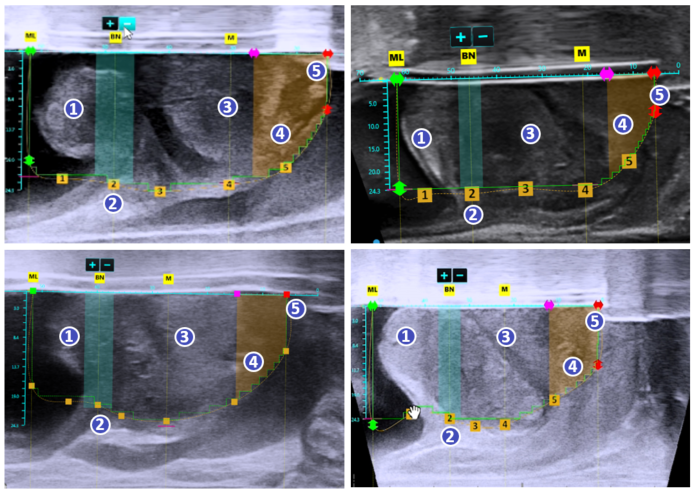

아쿠아 블레이션 수술 과정

초음파와 내시경을 동시에 실시간으로 확인하며 절제할 조직과 보존할 조직을 정확히 설계